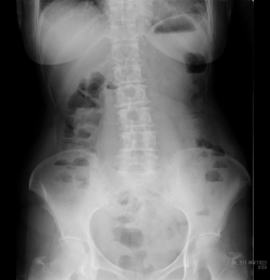

A 触診にておなかの状態を探り、大腸検査

画像検査、採血などで評価いたします。